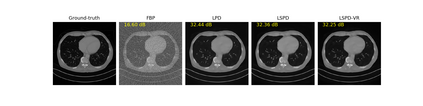

We propose a new type of efficient deep-unrolling networks for solving imaging inverse problems. Conventional deep-unrolling methods require full forward operator and its adjoint across each layer, and hence can be significantly more expensive computationally as compared with other end-to-end methods that are based on post-processing of model-based reconstructions, especially for 3D image reconstruction tasks. We develop a stochastic (ordered-subsets) variant of the classical learned primal-dual (LPD), which is a state-of-the-art unrolling network for tomographic image reconstruction. The proposed learned stochastic primal-dual (LSPD) network only uses subsets of the forward and adjoint operators and offers considerable computational efficiency. We provide theoretical analysis of a special case of our LSPD framework, suggesting that it has the potential to achieve image reconstruction quality competitive with the full-batch LPD while requiring only a fraction of the computation. The numerical results for two different X-ray computed tomography (CT) imaging tasks (namely, low-dose and sparse-view CT) corroborate this theoretical finding, demonstrating the promise of LSPD networks for large-scale imaging problems.